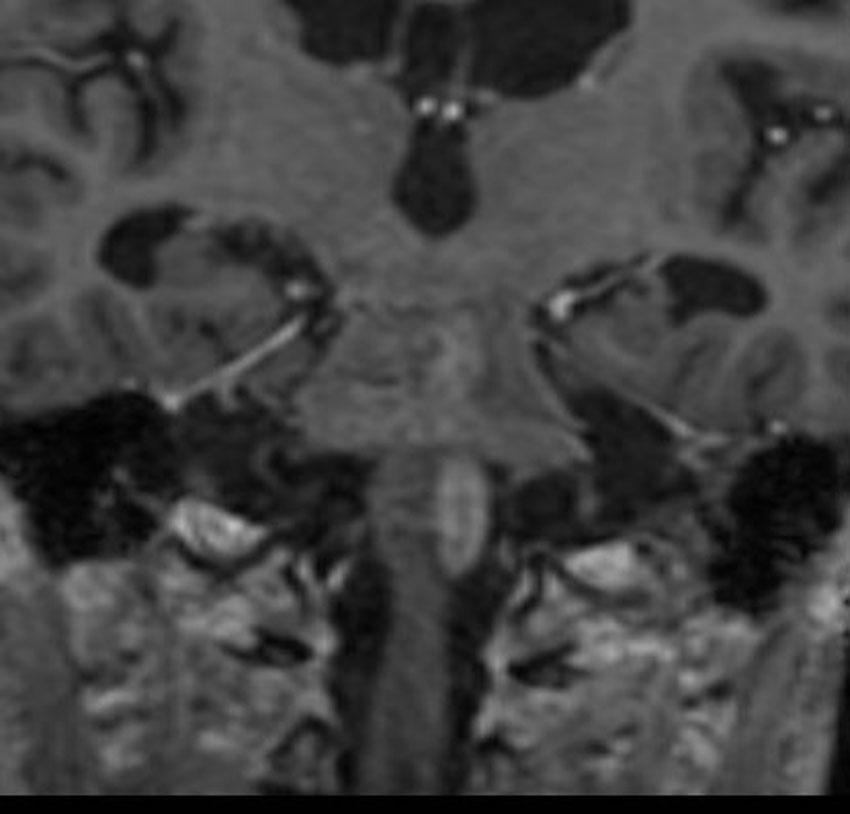

7年後のMRIです。延髄脊髄移行部(おそらくC1)に出血痕が残っています。放射線誘発海綿状血管腫といわれるものの画像所見ですが,ほんとのところは静脈閉塞によるうっ血症状と鬱血性の出血といわれています。